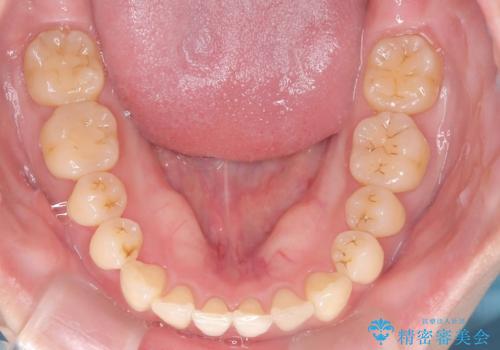

- 「下の前歯が斜めになっている」を主訴に来院された患者様です。

下顎前歯に叢生があり、右上2は反対咬合の状態でした。

下顎前歯の叢生がとれ右上2の反対咬合も改善し患者様にも満足していただけました。治療期間は1年~1年半を見込んでいましたが、患者様の協力もあり10か月で矯正を終えることが出来ました。